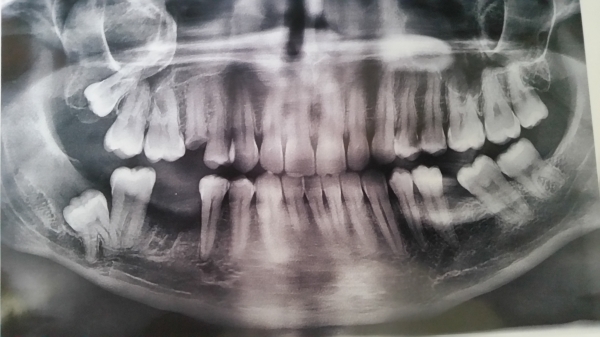

Нижняя правая восьмерка. Сам зуб не беспокоит, капюшон не мешает, но бывает из-под капюшона вытекает гной. Сказали надо удалять, но я что-то побаиваюсь, т.к. зуб целиком находится в костной ткани и близко к нижнечелюстному каналу.

Есть ли такая необходимость в его удалении, и насколько сложным и опасным оно будет?

Вам необходимо удалить все зубы мудрости. С 48 зубом рекомендую обратиться в ЧЛХ, так как Вы правы, корни данного зуба находятся в канале и после удаления продолжительное время у Вас будет парестезия (онемение). Но удалять крайне необходимо по причине того, что он повредит седьмой зуб, что в Вашем случае при отсутствии 46 будет очень нежелательно.